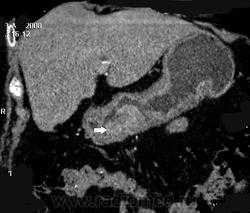

Первичный рак обычно обусловливает утолщение стенки в виде узла с неправильными контурами, ограничение растяжимости стенки, часто в сочетании с признаками вторичного поражения печени, регионарных лимфоузлов и, в некоторых случаях, сальника.

ГИСО желудка (стромальная опухоль) обычно возникает под слизистой оболочкой, обладает экзофитным типом роста. Слизистая над небольшими опухолями обычно не изменена, в то время как при образованиях большого размера происходит ее изъязвление, что, наряду с центральной кавитацией в образовании, может обусловливать обнаружение большой перигастральной опухоли, содержащей газ, жидкость, перорально принятый контраст.